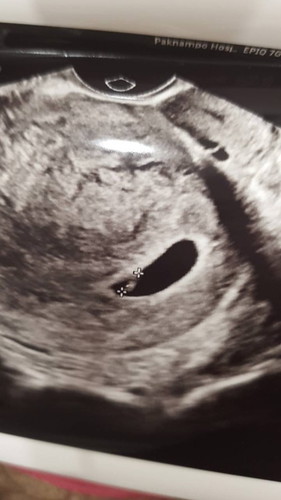

ถุงตั้งครรภ์

ถุงตั้งครรภ์แบบนี้ สวยหรือป่าวค่ะ 6w ค่ะ ท้องก่อนหน้านี้ท้องลมค่ะ รู้สึกกังวล

หมอบอกว่าไงบ้างคะ แต่เหมือนเห็นตัวน้องแลเวนะไม่น่าท้องลม